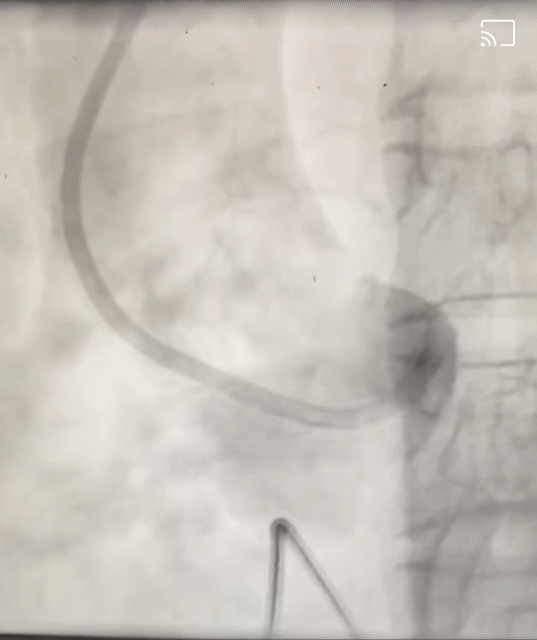

М, 55 лет, поступил в состоянии кардиогенного шока. На ЭКГ признаки окклюзии ствола левой коронарной артерии и переднего распространенного инфаркта миокарда.

Взят на ЧКВ. При введении контраста в область корня аорты в просвете аорты выявлен флоттирующий тромб, происходящий из устья левой коронарной артерии.

На картинке синим цветом обведён корень аорты (синусы Вальсальвы), зеленым - устье левой КА, желтым - проводник, по которому заводится контраст, красным - тромб